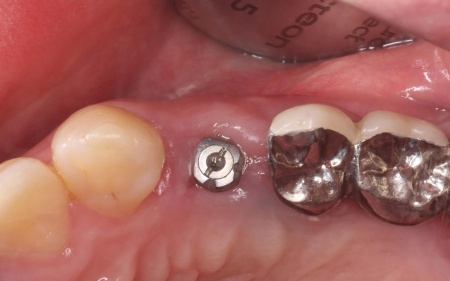

続いてインプラント手術を実施し、インプラントを正しい位置と角度で顎の骨に埋め込みました。

インプラント手術後は経過観察を行い、インプラントが顎の骨に結合したことを確認したら、インプラント上部に取り付ける人工歯を作製するために精密な型取りを実施します。

後日、完成した人工歯をインプラントに装着し、使用感や見た目に問題がないことを確認して、治療を終了しました。